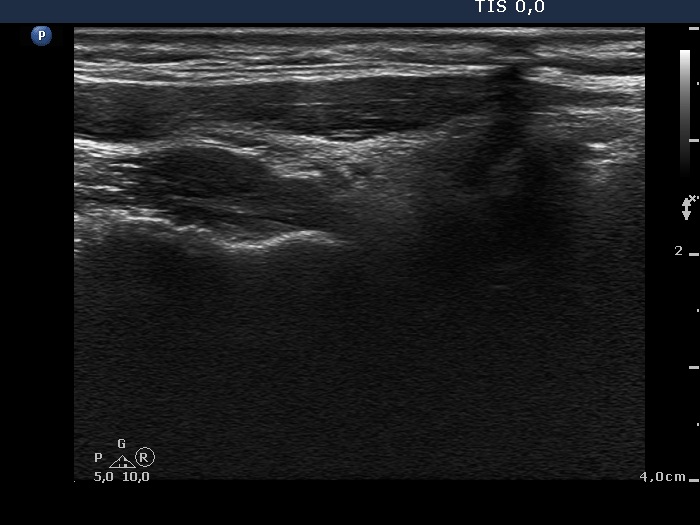

Ultrasound. Connective tissue replaced the thyroid parenchyma in both thyroid beds. There were tiny hypoechoic areas in the right thyroid bed. Two larger hypoechoic lesions were found, one in the isthmus and the other in the left thyroid bed. The latter presented vascularity.

Comment. The presentations of the hypoechoic lesion in all three sites were the same, they differed only in their size. Naturally, the two larger in the isthmus and in the left thyroid bed could cause and did cause concern. Especially that in the left lobe due to its intralesional vascularity. The larger lesions can correspond to small muscle fibers, remnant of the regenerative provess after the surgery but even damaged, non-viable thyroid tissue. Taking the thyroglobulin level into account, the risk of thyroid cancer is minimal but not zero.